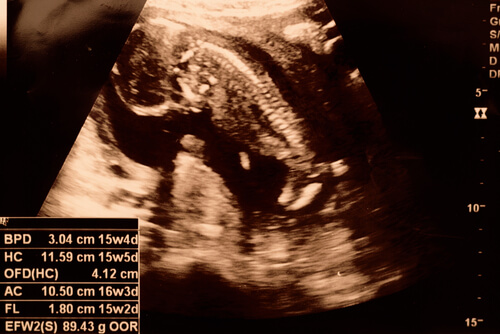

É possível que em algumas ultrassonografias o bebê já permita ver seu sexo. Além disso, os braços e as pernas vão crescendo e o bebê já consegue movimentar as articulações. Durante essa semana, o feto começa a desenvolver os pulmões, respirando o líquido ao redor. Da mesma maneira, ele consegue saborear alguns alimentos através do líquido amniótico.

Na 15ª semana de gravidez, o bebê ainda não está com o esqueleto formado. No entanto, sua espinhal dorsal com terminações nervosas pode ser vista. Além disso, ele é capaz de levantar o pescoço e as mãos. Na verdade, em algumas ultrassonografias o bebê pode ser flagrado com um dos dedos na boca.